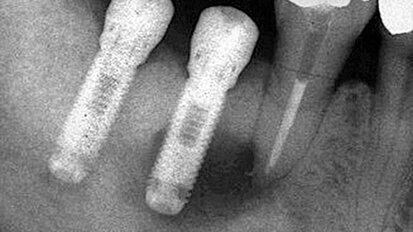

Periapikální léze implantátů a retrográdní periimplantitis – dva stavy nepříliš zdokumentované

Dentální implantáty jsou již v zubním lékařství zavedeny jako standardní protetické ošetření. Každý rok je zaváděno více a více ...